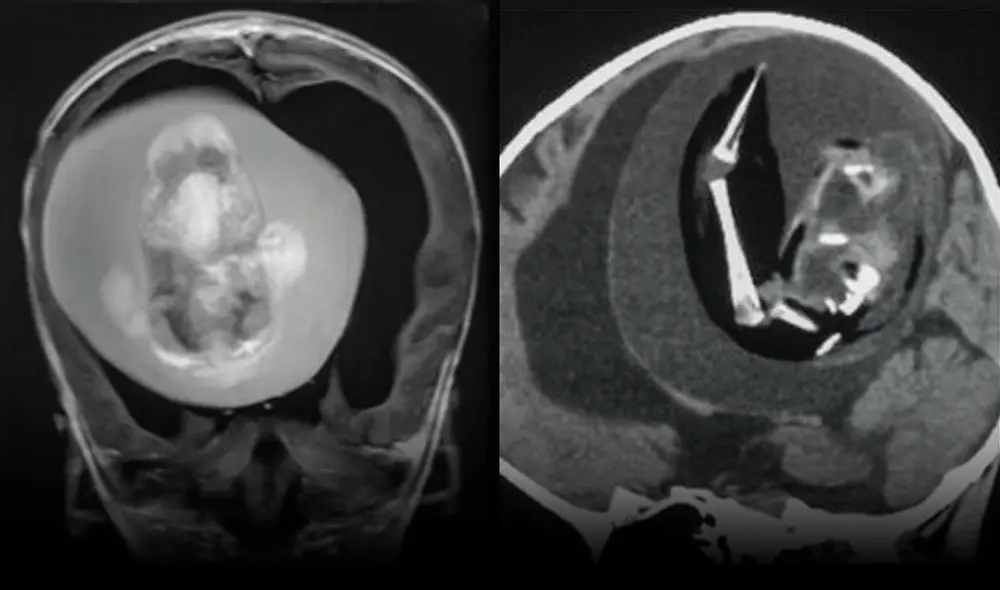

Una niña de 1 año fue sometida a una intervención quirurgica para extraer el feto de su hermano gemelo, anomalía conocida como "fetus in feto” (feto en feto) o "gemelo parásito”, según informó la Universidad de Fundan en Shangái, China. “Se identificó un fetus-in-fetu intraventricular, un gemelo diamniótico monocoriónico malformado, en una niña de 1 año con retraso motor y perímetro cefálico agrandado”, señala el reporte publicado el último 12 de diciembre de 2022.

El fenómeno ocurre aproximadamente a 1 de cada 500.000 nacidos. Usualmente, el feto malformado aparece en el abdomen; sin embargo, en este caso apareció en la cabeza de la menor.

Cuando eran fetos, ambos habían compartido la misma placenta, aunque separados por sacos amnióticos. Todo parece indicar que uno de ellos fue “absorbido durante la gestación” y se alojó en el cerebro de la niña durante el proceso de desarrollo, denominado plegamiento de la placa negral.

El descubrimiento se dio luego de que la menor diera señales de retrado en el desarrollo de sus habilidades motoras, agrandamiento en la circunferancia del craneo y acumulación de líquido en el cerebro.

Los escáneres cerebrales revelaron que el feto en la cabeza de la niña tenía columna vertebral y dos huesos de la pierna. Además, tenía espina bífida —afección donde parte de la médula espinal queda expuesta— y, cuando fue extraído, se determinó que tenía brotes de extremidades superiores y dedos.